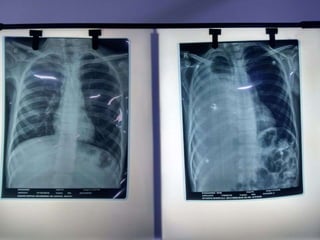

• At second admission similar examination findings,

• neutrophilic leukocytosis, empirical cefipime plus tazobactum,

• CXR increased right parapnumonic effusion, ICD placed, serial CXR no

complete expansion,

• Thought loculated empyema, underwent right thoracotomy and

decortication, intra operative sample for culture sterile.

• Complete lung expansion post procedure .